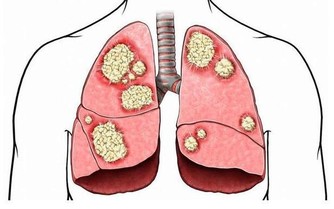

1、胸悶氣短: 一些業主在搬進新家後常常感覺到胸悶氣短、呼吸不暢,但去醫院檢查又沒有發現任何心肺問題,這種情況很有可能是甲醛中毒引起的。胸悶是甲醛中毒常見症狀之一,一般在輕度或中度中毒時出現。所以,如果時常在家中感到胸悶,首先應去醫院排除心臟問題,然後再確定是否是甲醛超標造成的。

2、呼吸系統刺激: 回家開門的一瞬間,家的溫馨氣息就會撲面而來,但新家不是這樣,新業主每次回家聞到的第一縷空氣往往伴隨刺鼻的化學品氣味,怎麼會感受到溫馨呢?這種裝修特有的刺鼻氣體的主要有害成分就是甲醛,多數家庭可在通風一個月時間明顯減輕(注意減輕並不等於消除),但如果通風一個月還沒有改觀,那就應該考慮治理室內空氣污染了。

5、頭暈、乏力、嗜睡: 甲醛可影響人的造血系統,輕則引發貧血,嚴重的甚至可能導致白血病。有調查指出,醫院血液科病房中三成以上白血病患者的家庭在兩年內進行過裝修。而兒童因裝修患病的機率更高,佔患病兒童的半數以上。當人體血液供應不足時,就會經常感到疲憊,走路都沒有力氣。因此,入住新居後有頭暈、乏力、嗜睡的症狀,應及時去醫院檢查血常規。